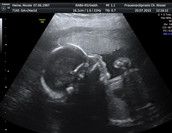

Hallo,ich bin neu hier und bräuchte mal einen Rat. Und zwar ist es bei mir so,das mein Junge in der Beckenendlage liegt. Daher wird ein Kaiserschnitt gemacht. Nun ist es so,das ich nur noch sehr wenig Fruchtwasser hab,mein Mutterkuchen verkalkt ist und mein Gebärmutterhals nur noch 19 mm ist. Mir geht es damit auch nicht mehr gut. Das Sodbrennen drückt mir jede Mahlzeit wieder hoch und ich bin auf Grund der Komplikationen momentan nur noch ein reines Nervenbündel. Ich mach mir Sorgen , daß es meinem Jungen nicht mehr gut geht. Morgen muss ich zur Kontrolle ins Krankenhaus und ich wollte wissen, ob ich sagen kann,das der Kaiserschnitt sofort gemacht werden soll, weil es mir damit nicht mehr gut geht? Ich bin 36 Ssw und Lungenreife hab ich auch schon erhalten. Mein Junge wiegt ca 2500 Gramm und ist ca 45 cm.